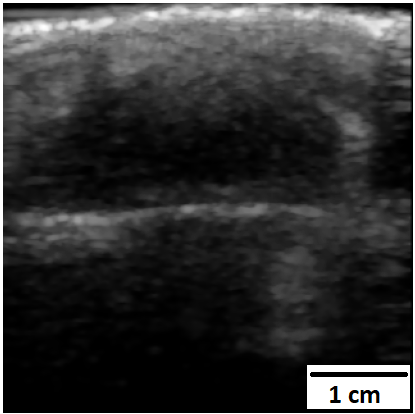

Figure 2: (a-d) Four representative US wound images. (e-h) Visualization of corresponding segmentation predictions for FCN. Green indicates correct matches, red and yellow indicate missed (false negative) and oversegmented (false positive) areas, respectively.

Table 2 shows the quantitative evaluation of the algorithms. U-Net and FCN both achieve a Dice score of 0.340.340.34 compared to pre-trained ResNet-U-Net which has a Dice score of 0.270.270.27. Visualizations of the segmentation results for FCN are shown in Figure 2, where (a-d) are the original inputs, and (e-h) the corresponding color-coded outcomes. In general, the performance is promising for a number of cases, although we see a high FP rate (d,h) for others. Table 3 shows the ratio of m¯rsubscript¯𝑚𝑟\overline{m}_{r} for different wound regions compared to m¯wsubscript¯𝑚𝑤\overline{m}_{w} of the whole wound area. In the wound center, the US values are lower (ratio: 0.89 ±plus-or-minus\pm 0.11), compared to the wound borders (ratio: 1.47 ±plus-or-minus\pm 0.37).

In this work, we showed a proof-of-concept for a non-invasive imaging technique paired with machine learning. We performed initial experiments for automatic segmentation of US wound images with deep learning which show an Dice score of 0.340.340.34 for both U-Net and FCN and 0.270.270.27 for ResNet-U-Net. The segmentation results strongly depend on the quality of the scan and the specific wound type. Quantitative results can still be improved but the visual examination of the results indicates applicability of the proposed setup. For images illustrated in Figure 2(e-g), the segmentation is very good. However, the network misclassifies the region beneath the hyperechoic bone surface (image h) as this region therefore appears dark and similar in intensity to the wound region.